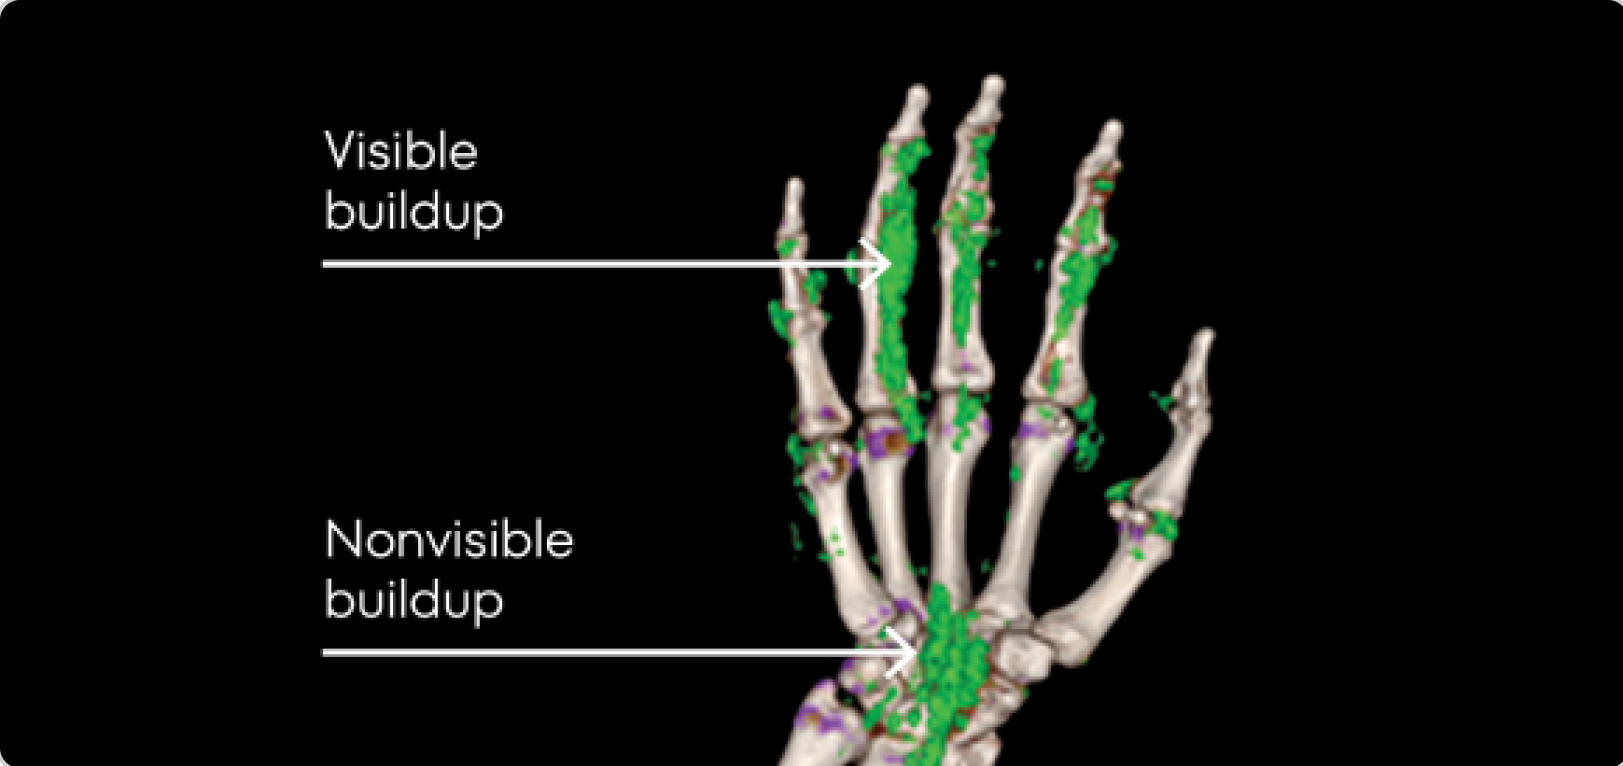

Dual Energy CT scan of hand showing visible and nonvisible buildup in gout patient

DECT OF URATE BUILDUP

DECT image courtesy of Dr. Jurgen Rech. Green areas indicate urate crystal buildup.

DECT, dual-energy computed tomography.

KRYSTEXXA is not indicated for treatment of pain.

Up to 75% of the urate burden may not be detected upon physical examination1